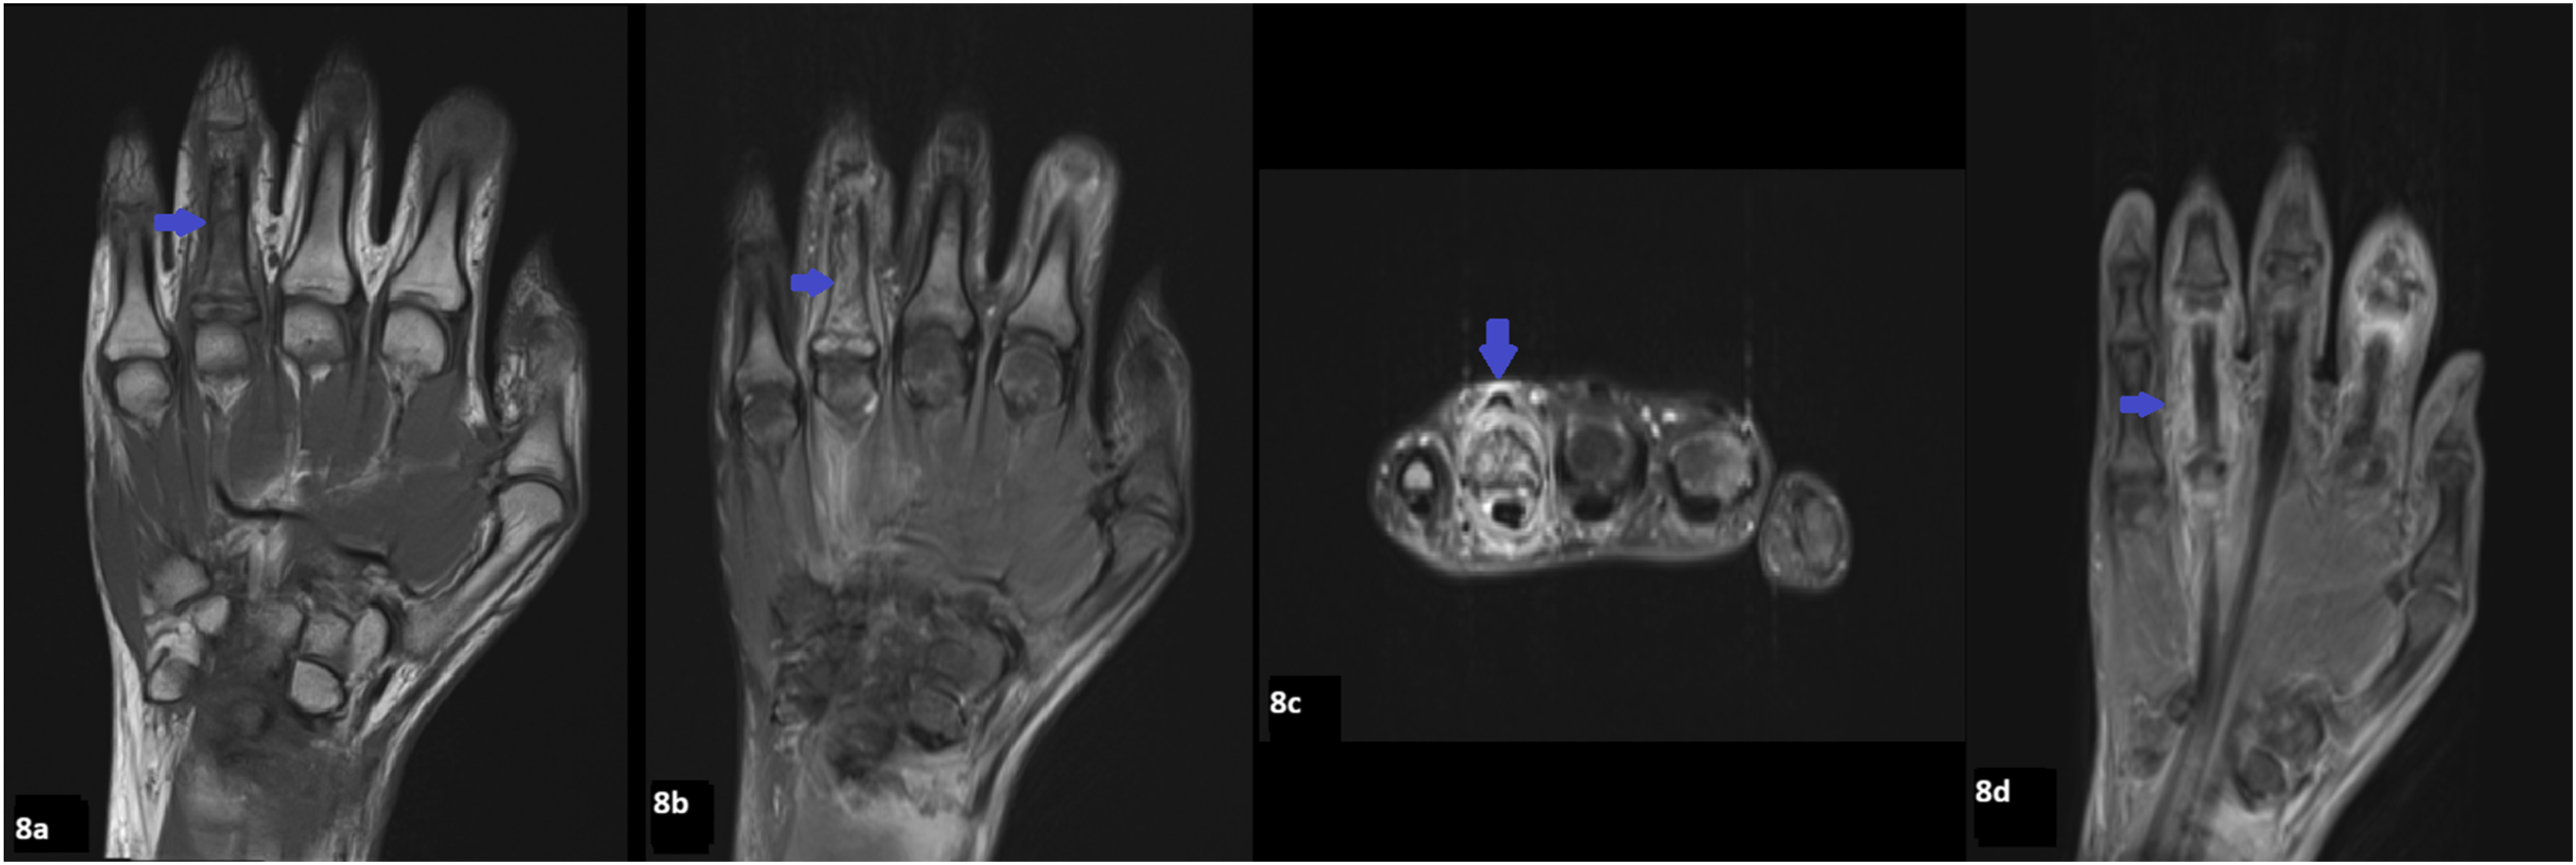

Radiographs of the hands revealed multifocal permeative lucencies involving the distal radius and multiple phalanges (Figure 5), raising concern for systemic arthropathy or osteomyelitis. MRI of the hands showed bone marrow signal abnormalities consistent with multiple bone infarcts (Figures 6–8). Radiographs of the hand showing permeative lytic lesions involving left distal radius and multiple phalanges (blue arrows). (a) Coronal T1W and (b) Coronal STIR MRI of the right hand reveals bone infarcts at the scaphoid and middle finger proximal phalanx. (a) Coronal T1W and (b) STIR MRI of the left hand demonstrates patchy T1 hypointense signal and STIR hyperintense signal abnormality at the distal radius representing ischemic changes. (a) Coronal T1W, (b) Coronal STIR, (c) Axial STIR, and (d) Post contrast T1FS of the left hand demonstrates bone infarct at the ring finger proximal phalanx, and soft tissue edema and enhancement.